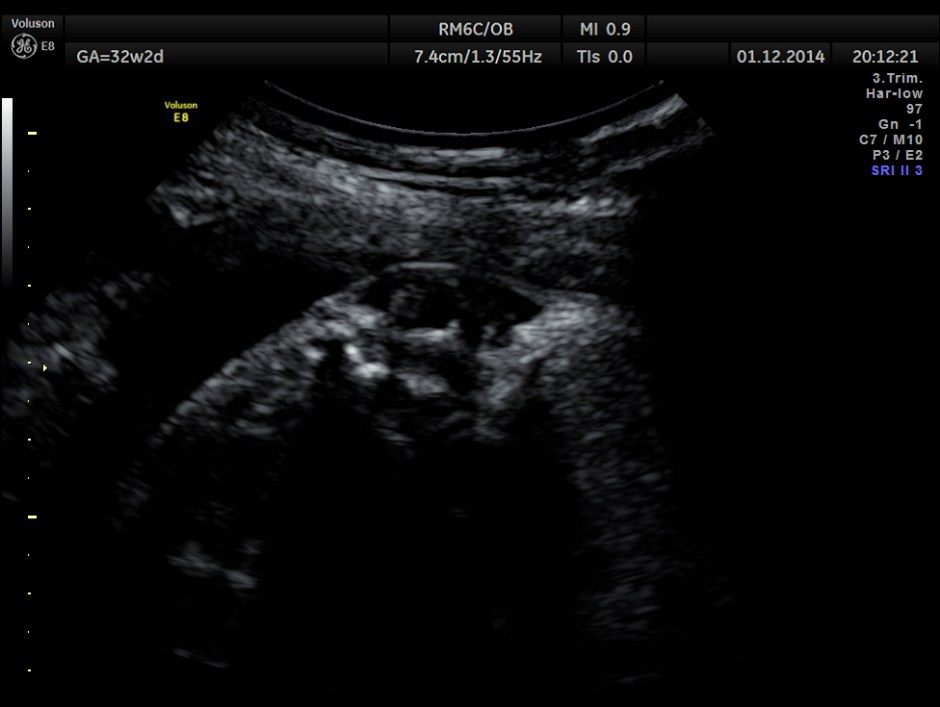

Careful examination revealed a neural tube defect with meningo myelocele at the lumbo sacral level.

Spinal deformity was also noted.